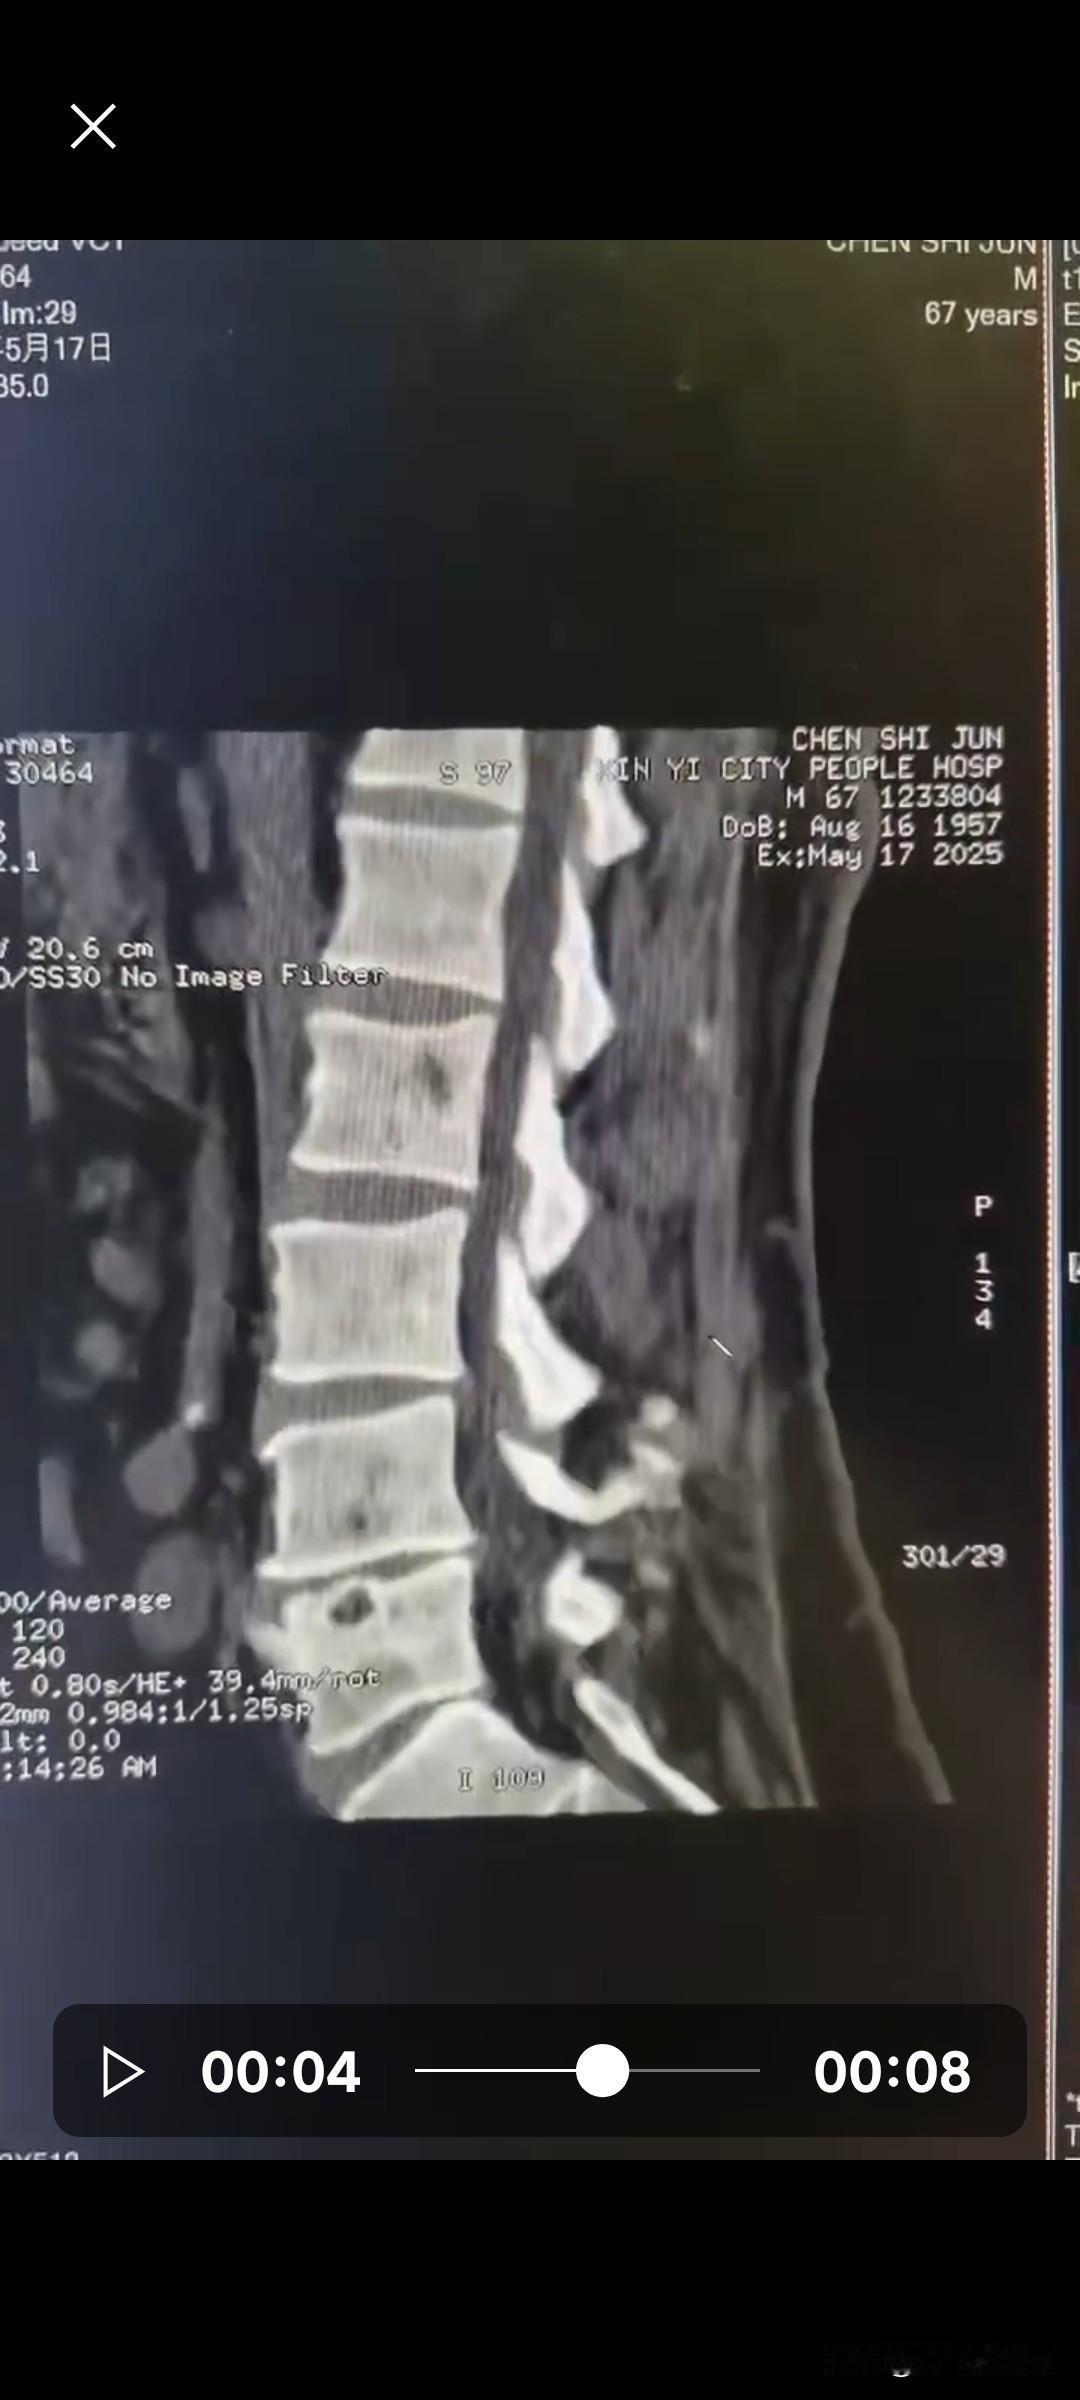

我乡下有个本家亲戚,在县医院查出腰椎间盘突出,需要做手术治疗。科室主任跟他说:“这个手术我们科室本身也能做,现在大家条件都好一些了,不如请上海的专家过来做,手术会更稳妥,术后恢复也更快。要是愿意,我可以帮忙联系上海专家,但需要病人私下支付2万元作为专家出诊的辛苦费。这个钱不能报销,也不能微信转账,只能给现金。” 亲戚现在很为难,专门来问我该怎么办。腰椎间盘突出手术毕竟不是小事,主任也说了,本地医院能做,但请专家来做效果更好。可如果不在当地做手术,就得转院去上海,主任可以推荐医院和专家。但去了之后还要排队等床位,不知道要等到什么时候,等待期间吃住也是一笔不小的开销,确实是个两难的选择。网友们,请问遇到这种情况到底怎么样做比较稳妥?请大家帮忙支个招!在线等!